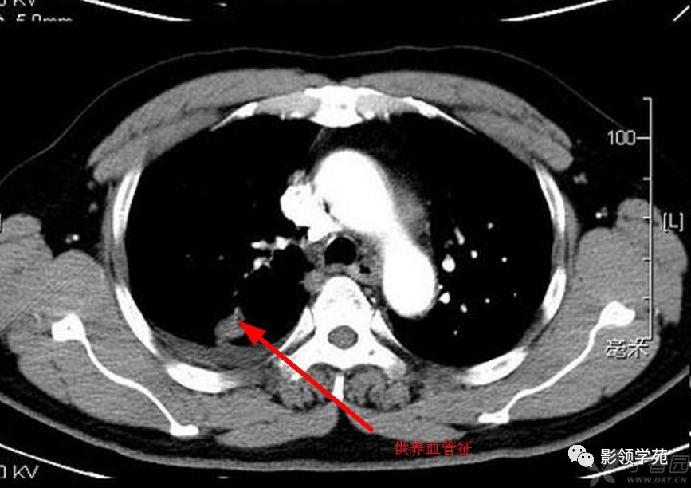

结节或肿块周围可见晕轮征、供养血管征。晕轮征提示肺结节或肿块出血,CT表现为结节或肿块周围磨玻璃密度影;供养血管征CT表现为血管影进入结节或肿块内,提示病变以血管为中心生长。

病例4:左肺斑片状实变,右肺中下叶结节灶,中叶结节见供养血管征。